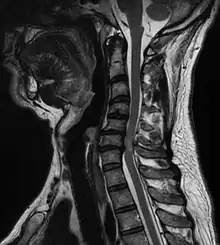

| A tumour causing spinal cord compression | |

Spinal cord compression is a form of myelopathy in which the spinal cord is compressed. Causes can be bone fragments from a vertebral fracture, a tumor, abscess, ruptured intervertebral disc or other lesion.

Diagnosis is by X-rays but preferably magnetic resonance imaging (MRI) of the whole spine.[3][4]